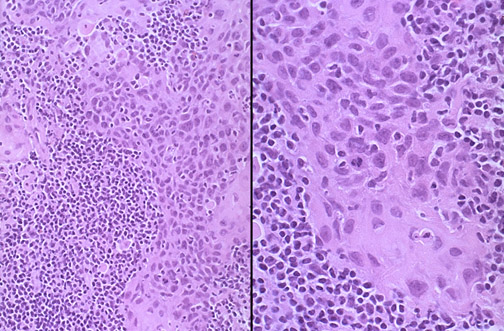

Seen here at medium and high microscopic magnification is a nasopharyngeal carcinoma. These carcinomas have features of squamous cell carcinoma with a prominent lymphoid component. Many are associated with Epstein-Barr virus (EBV) infection.